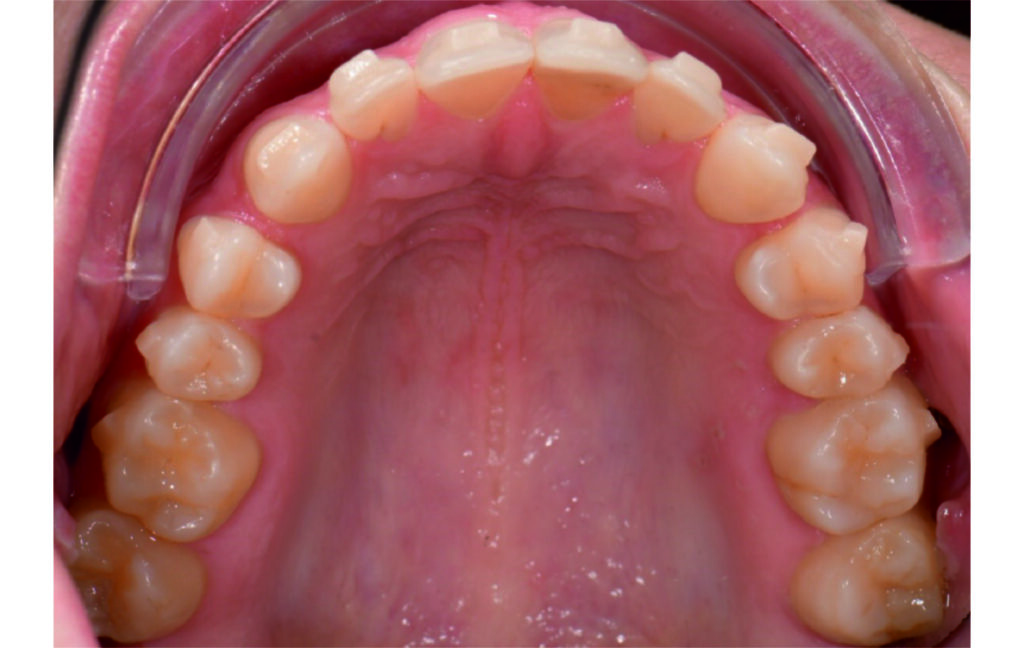

Initial Photos and datas

Angle Class II 2mm on the right, Angle Class II 2mm on the left, light mandibular asymmetry to the right, lower central line 1mm to the right, upper central line 1,5mm to the left, 1mm overjet and overbite. Sagittal asymmetry of upper dental arch. Light crowding upper and lower frontal segments, severe attrition of posterior teeth, night bruxism. Normal sagittal position of both jaws, high angle case, steep mandibular ramus,excessive lower facial height, open bite tendency.